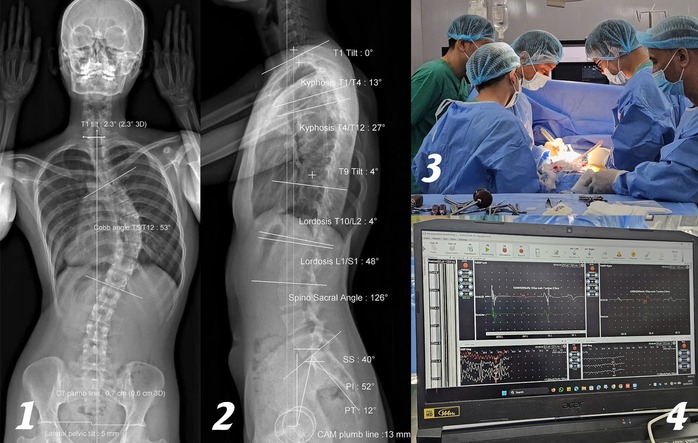

Hình ảnh EOS cho thấy người bệnh vẹo cột sống ngực 53 độ. Sau đó, các bác sĩ tiến hành phẫu thuật cùng với hệ thống IOM cảnh báo thần kinh trong phẫu thuật cột sống.

Tại đây, D. được chụp EOS (chụp quang tuyến thấy toàn bộ trục xương của cơ thể) và thăm khám. Kết quả cho thấy cột sống cô bị vẹo 53 độ, mức độ nghiêm trọng, có nguy cơ ảnh hưởng đến thẩm mỹ, tâm lý và chức năng vận động nếu không được điều trị kịp thời.

Trong quá trình phẫu thuật, các bác sĩ đã tính toán kỹ lưỡng, nắn chỉnh các đốt sống bằng hệ thống vít ốc chuyên dụng để giúp cột sống của cô trở lại mức sinh lý nhất có thể. Sau 4 giờ, ca phẫu thuật thành công.

Điểm nổi bật của ca phẫu thuật này là việc ứng dụng hệ thống IOM (theo dõi điện sinh lý thần kinh trong mổ). Hệ thống này giúp giám sát liên tục tín hiệu thần kinh, kịp thời cảnh báo nguy cơ tổn thương tủy sống, biến chứng nặng có thể dẫn đến liệt. Nhờ đó, ê-kíp phẫu thuật có thể điều chỉnh thao tác ngay trong quá trình mổ, đảm bảo an toàn tối đa cho chức năng vận động của bệnh nhân.